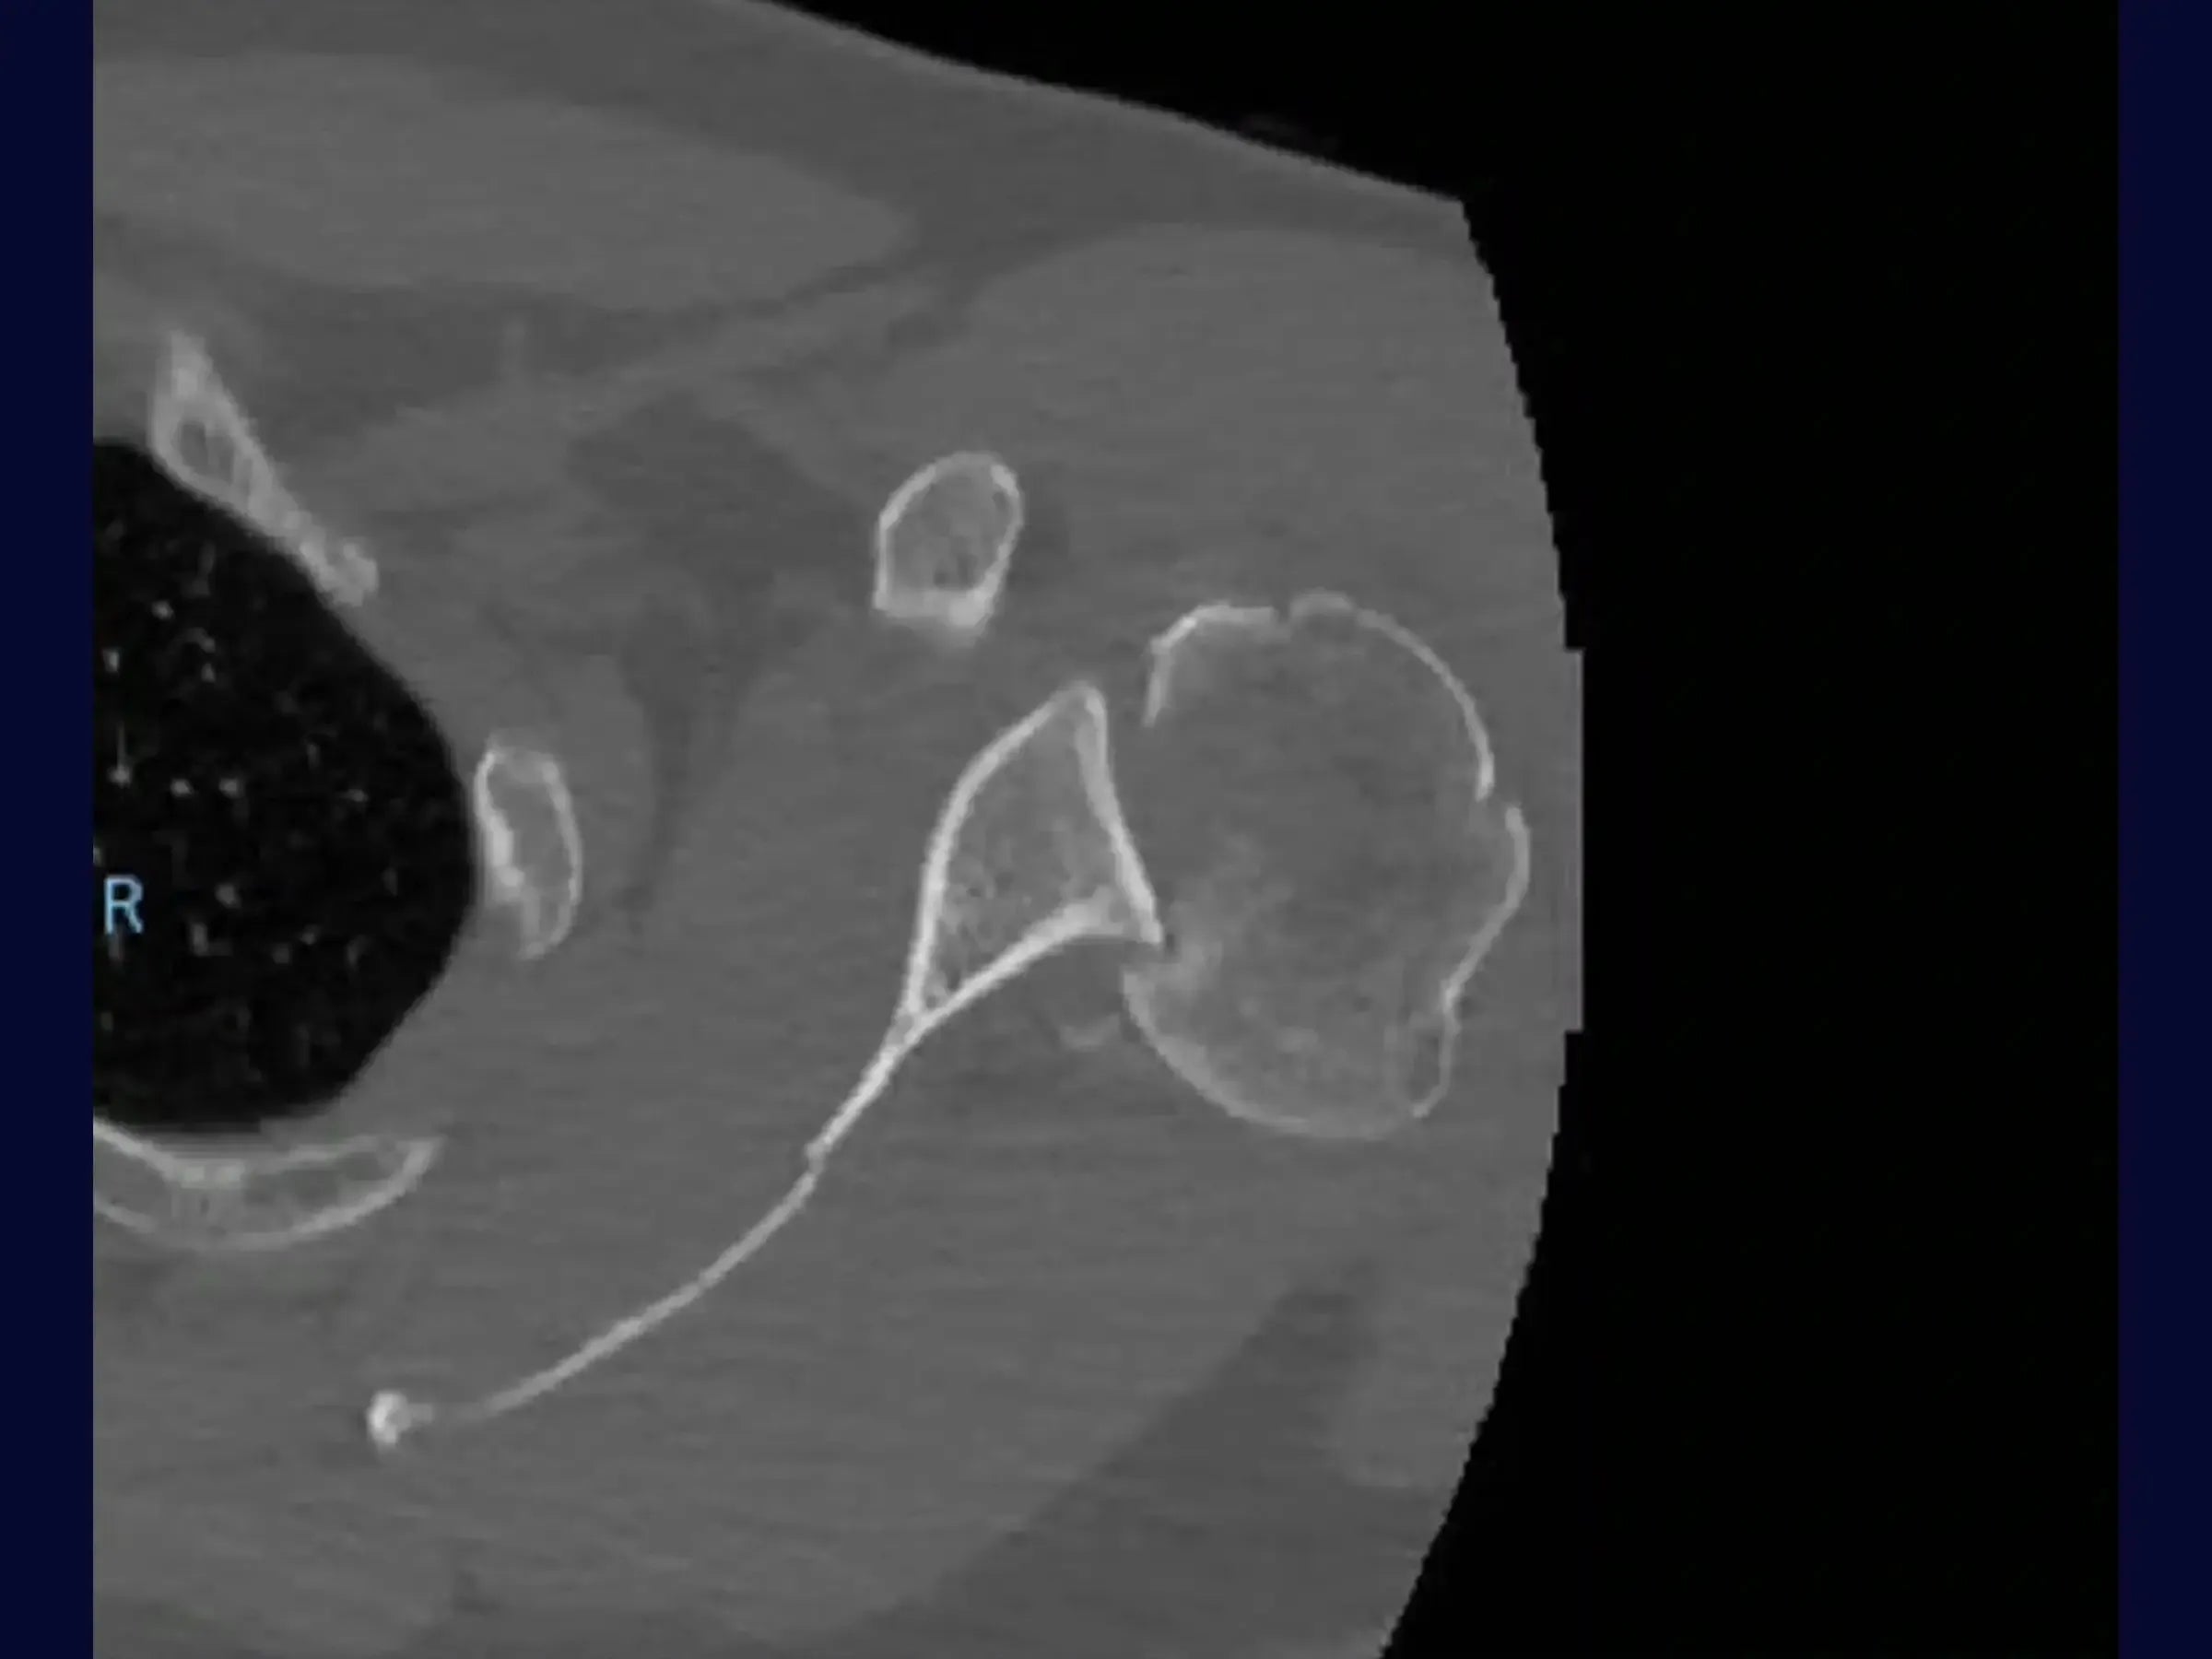

Domine o tratamento de luxações posteriores do ombro com impactação da cabeça umeral, um desafio técnico que exige precisão para evitar a progressão do traço de fratura. Este treinamento oferece uma imersão na abordagem cirúrgica, detalhando manobras de redução e fixação com placa de fibra de carbono, apresentada sob a perspectiva cirúrgica.

- Identificação Estrutural Profunda: Estratégias para delimitar a cabeça do úmero em profundidade e inserir afastadores em casos de difícil acesso.

- Manobras de Redução Controlada: Técnicas para tentar a redução da luxação com fios de alta resistência, focando na prevenção da fragmentação completa da cabeça umeral.